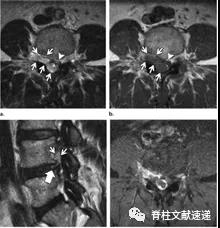

图注:背侧硬膜外椎间盘突出

图注:术前诊断倾向于硬膜外脓肿,术中见病灶呈致密纤维状,组织病理学检查显示纤维软骨盘伴反应性改变。